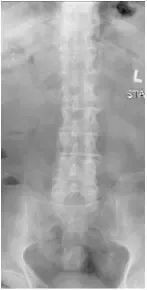

X-rays and MRI of the Lumbar spine showed L4-5 degenerative spondylolisthesis

and severe spinal stenosis.